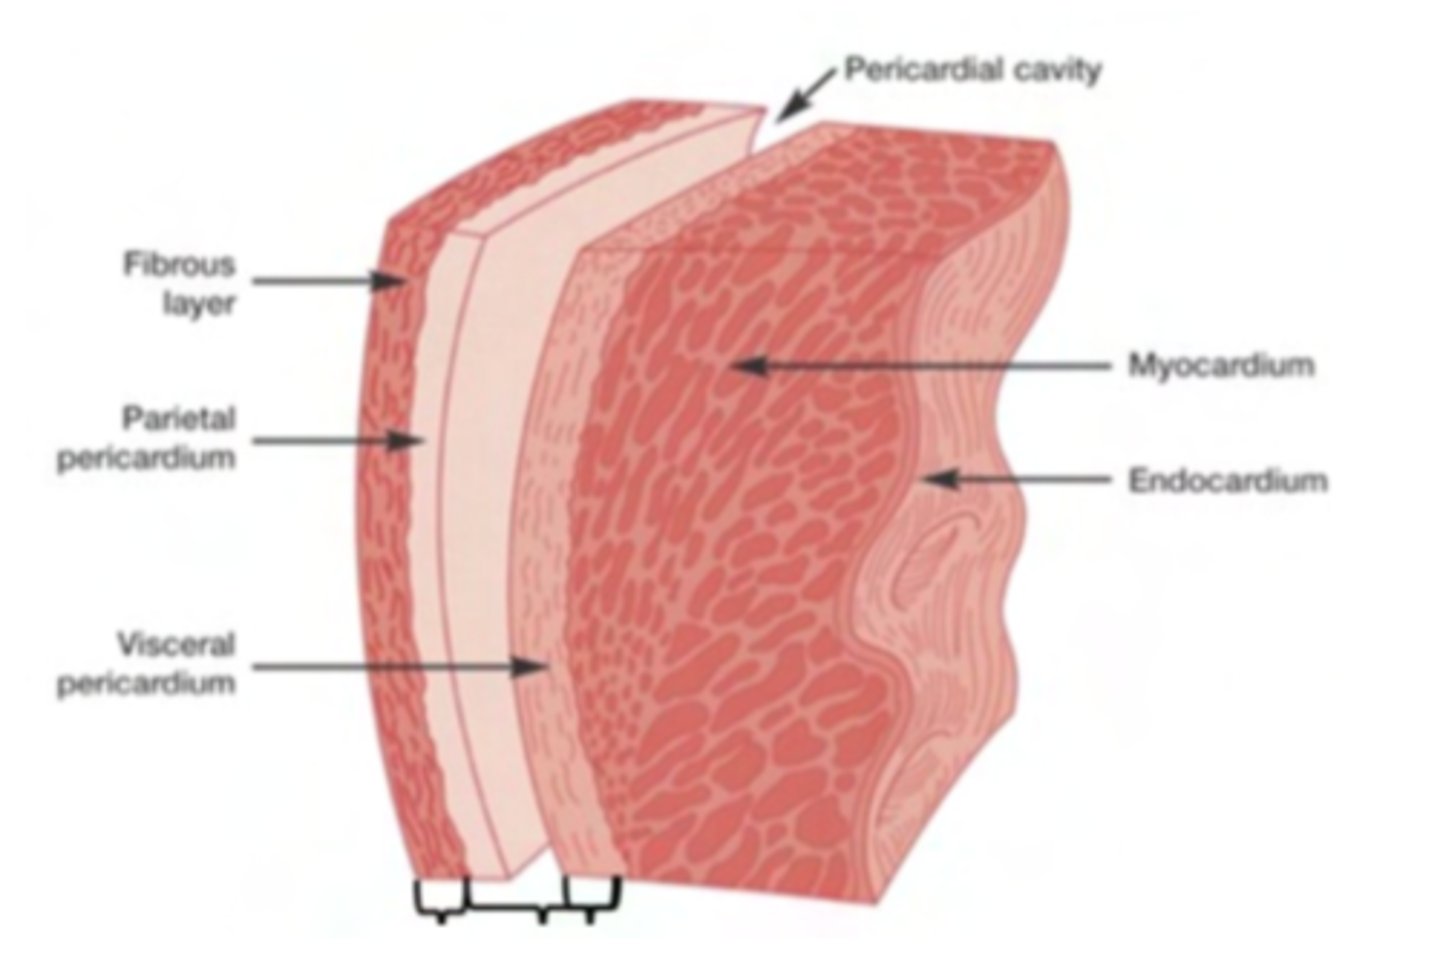

What are the layers of the pericardium?

The pericardium consists of two main layers:

- the fibrous pericardium

- the serous pericardium

How is divided the serous pericardium?

. Visceral layer or Epicardium (innermost). Adheres to the heart

. Parietal layer (outermost)

Between these layers is the pericardial fluid (pericardium cavity )

What is the fibrous pericardium?

the tough, outer layer

protects the heart

maintains its position in the thorax.

defines the boundaries of the medium mediastinum